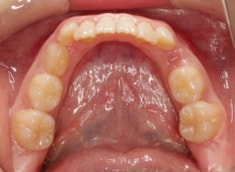

治療後(1年5ヶ月後)

治療開始から11ヶ月